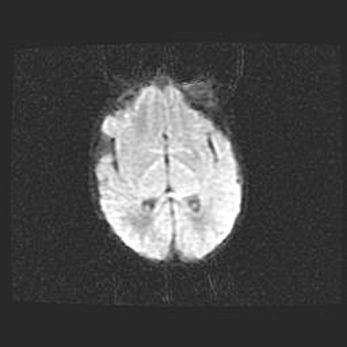

Неполная лизэнцефалия (пахигирия). Открытая гидроцефалия.

Возраст: 17 дней

Вес: 3110 г

Пол: мужской

Окружность головы: 33,5 см

Срок гестации: 35-36 недель

Лизэнцефалия—недоразвитие корковой пластинки и мозговых извилин в результате нарушения миграции нейронов коры. Поверхность мозговых полушарий гладкая. Микроскопически выявляется отсутствие нормальных слоев коры и скопление групп нейронов в подкорковом белом веществе.

Пахигирия—уменьшение числа вторичных извилин. В пораженном полушарии нервные клетки образуют толстый недифференцированный слой с неправильно расположенными нервными волокнами и группами гетеротопных клеток. Нервные клетки незрелые. Белое вещество истончено. При этом нередко аномально развит корково-спинномозговой путь.